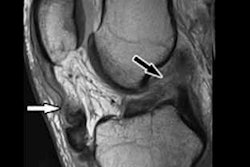

Image shows fiber tractography of the biceps femoris muscle at the three study time points for one marathoner. The fiber tracts are color-coded to show the changes in mean diffusivity. Image courtesy of Radiology.Tensor eigenvalues and mean diffusivity remained significantly elevated in the biceps femoris muscle three weeks after the run.